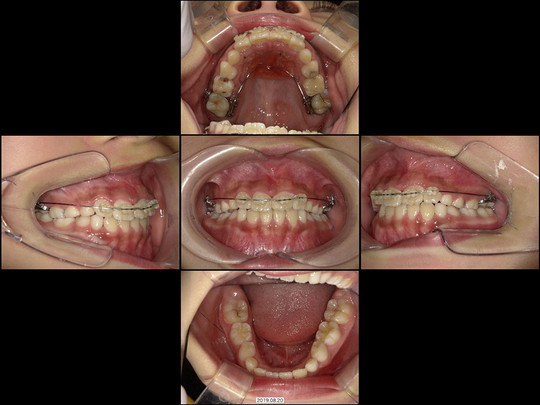

Sさん 初診時9歳 女性

矯正治療中

治療の説明

上の前歯2本が生えてこないのを心配しておられたのに、「様子見しましょう」とずっと言われ続けてお困りでした。中には「大学病院でしか対応できません」と言われたこともあったようです。

CT検査の結果、歯が歯ぐきの中に埋まった埋伏(まいふく)といわれる状態でした。歯ぐきだけでなくあごの骨まで歯に被さっていたため、埋伏している前歯の表面を傷つけずにあごの骨まで削り、引っ張り出すための外科処置(外科的開窓牽引による矯正)を行いました。奥歯の乳歯から永久歯への生え変わりのスペースもないので、あわせてあごの骨も拡大しています。

40か月、40回

541,000円

リスクや副作用:出血を伴う可能性があります。治療後に、痛みや腫れ、出血を引き起こす可能性があります。

装置に慣れるまでに1週間ほどかかる可能性があります。歯列を広げる過程で少し痛みを感じる可能性があります。装着時に多少しゃべりづらくなる可能性があります(2~3週間ほどで慣れます)。